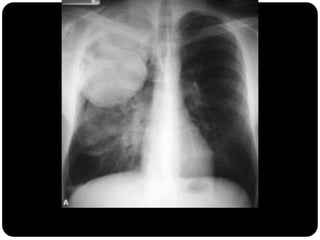

Nódulos pulmonares múltiplos

 Causas mais comum em adultos:

neoplasia metastática (diversos diâmetros,

densidade de tecido mole, raramente calcificada, exceto

osteossarcoma)

doença infecciosa (fúngicas e micobacterianas);

Carcinoma de tireóide com metástases pulmonares;